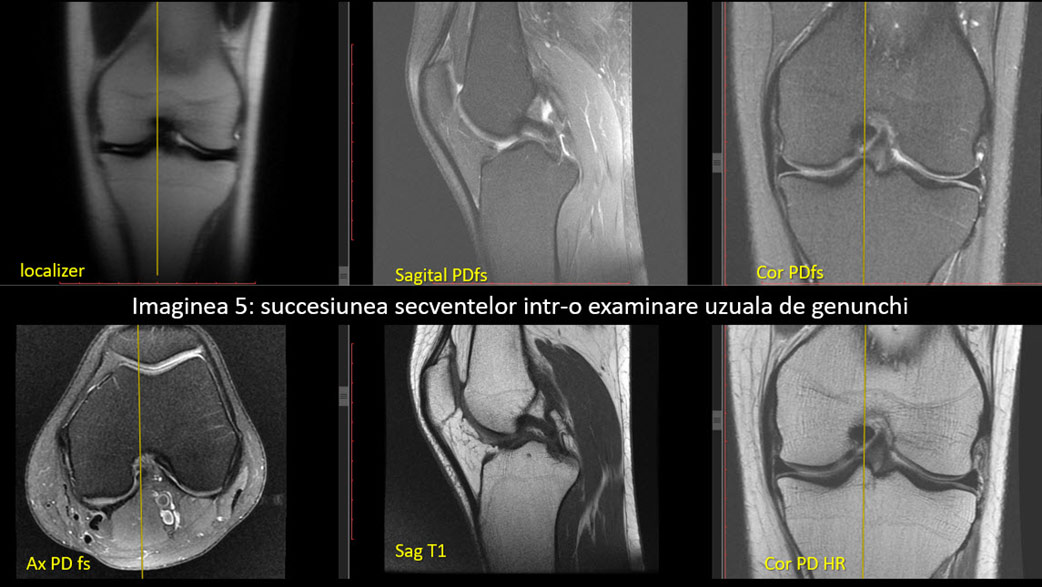

Secvențele IRM genunchi uzual

Parametrii:

FOV 16

Matrice cel puțin 320/320

Slice 3mm, gap 0.3

TR – 3000-5000

TE 30-55

Matrice 384/320

TE 30-55 (pe măsură ce creștem TE, ne apropiem de secvențele cu TE intermediar, între PD și T2)

Matrice 320/320

TE 30-50 (pe măsură ce creștem TE, ne apropiem de secvențele cu TE intermediar, între PD și T2)

TR – 400-800

TE 10-15

FOV 14

Matrice 384/384

Slice 2.5mm, gap 0.2

TE 30-50